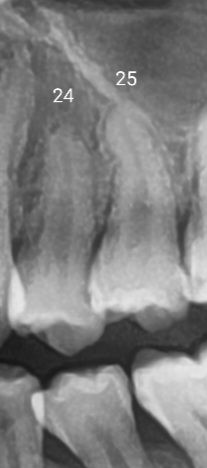

24번 25번 치아 충치있나요 파노라마

24번 25번치아 인접면에 충치있나요 있다면 치아당 왼쪽에있는지 오른쪽에 있는지 아니면 양쪽에있는지 상세히 알려주시면 감사하겠습니다

24번과 25번 사이에 인접면 충치가 있는 것처럼 방사선상에서는 보이고 있습니다.

하지만 자세한 확인을 위해서는 조금 더 치아에 평행이 되어 사진을 찍는 것이 좋으며 육안으로도 확인이 가능해야 할 것으로 생각됩니다 자세한 확인을 위해서 치과에서 진료를 받아 보세요

치아 사이에 충치가 잇는것처럼 보입니다. 치아 상태에 따라서 레진 또는 인레이 치료를 하셔야될수도 잇을것같습니다.

인접면 충치는 이렇게 치아끼리 겹쳐있는 사진, 특히 해상도가 낮은 파노라마 방사선 사진으로는 판별이 쉽지 않습니다. 교익 방사선 사진 (작은사진)이 필요합니다.